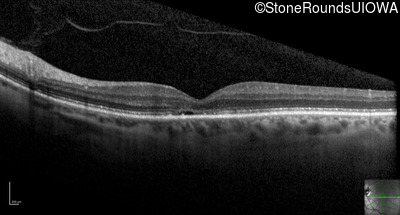

Optical Coherence Tomography - Left - 20/125

Exemplar / OCT Stack

OCT Stack